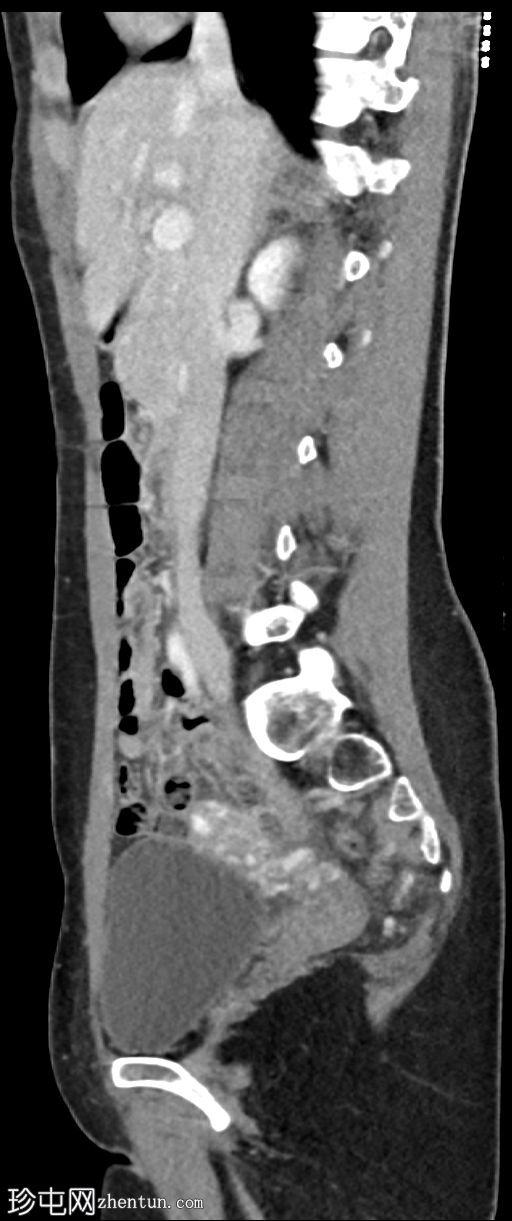

矢状位增强扫描(门静脉期)

左肾肾盂肾盏系统及左侧输尿管,管壁环周增厚及强化,符合肾盂输尿管炎的影像学表现

左肾实质强化正常,无肾周脂肪浸润

膀胱充盈良好,无管壁增厚或周围脂肪浸润

无尿路结石

偶然发现肠系膜有一2.2 x 4 x 3.2 cm大小的边界清晰的均匀脂肪密度病变,符合肠系膜脂肪瘤的影像学表现

左侧卵巢静脉明显